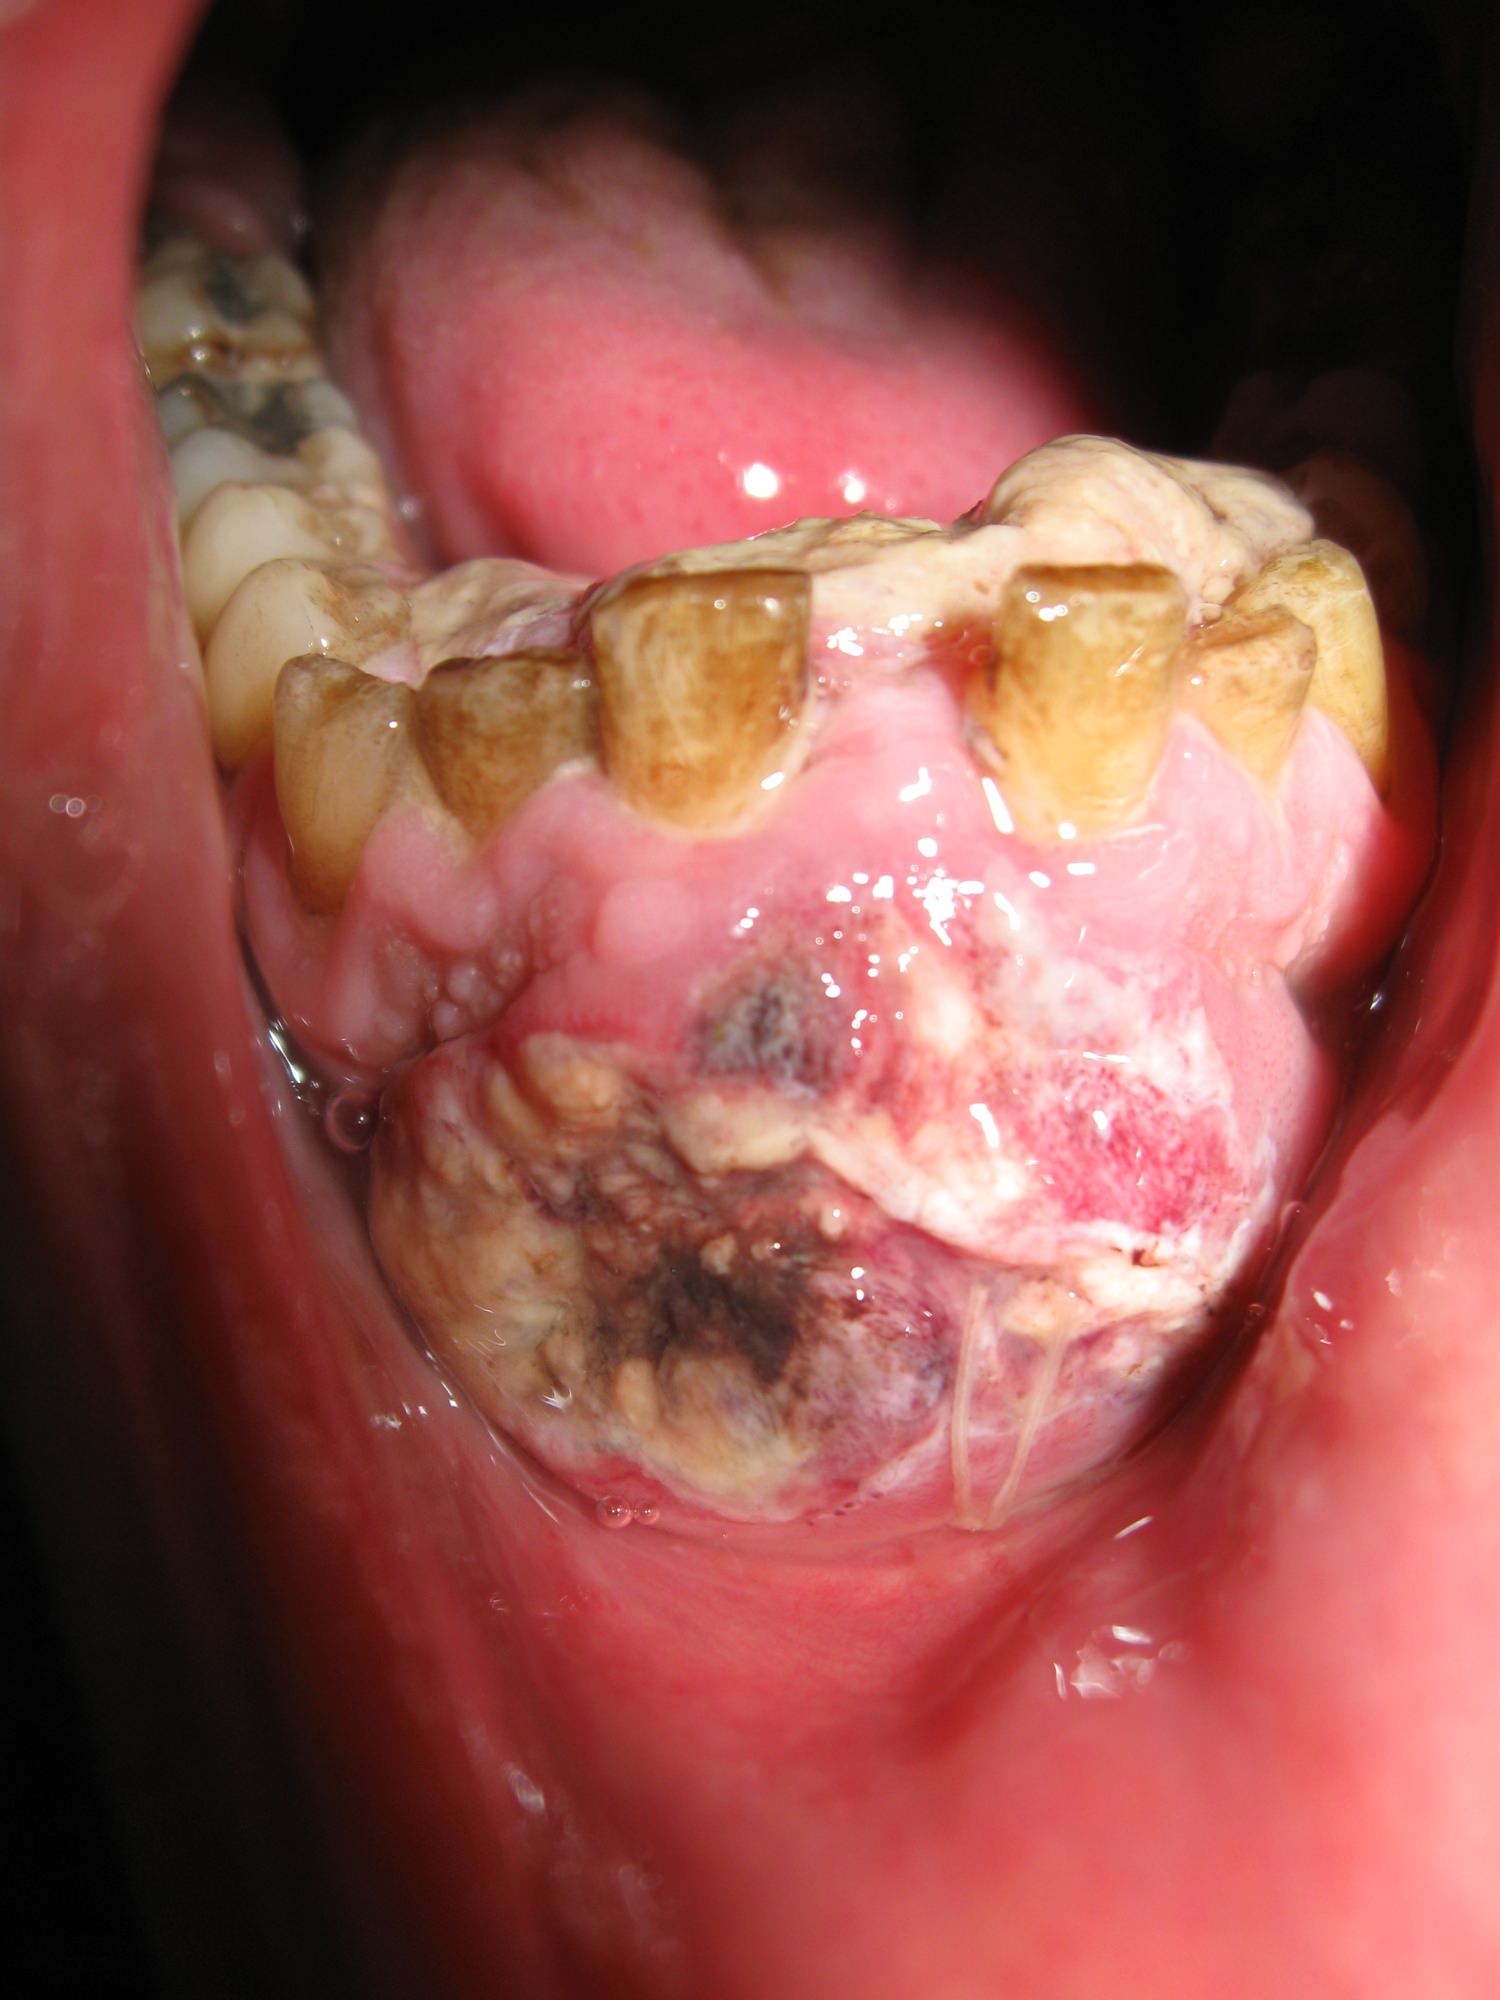

Рак ротовой полости